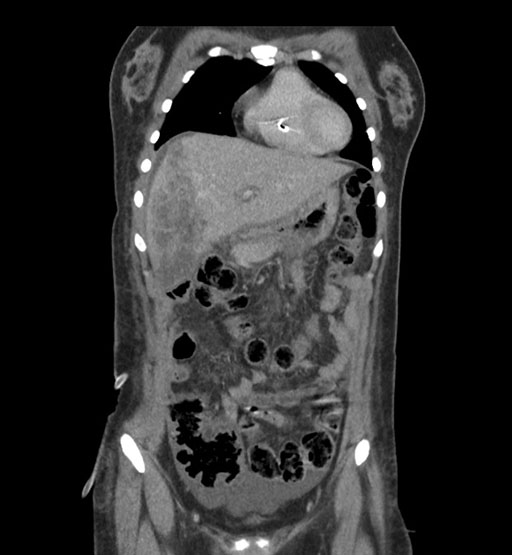

Imaging Analysis

Look through the patient's CT scan to identify any areas of concern for the necessary procedure.

Coronal Arterial

Based on initial findings, which issue(s) would you be most concerned about?